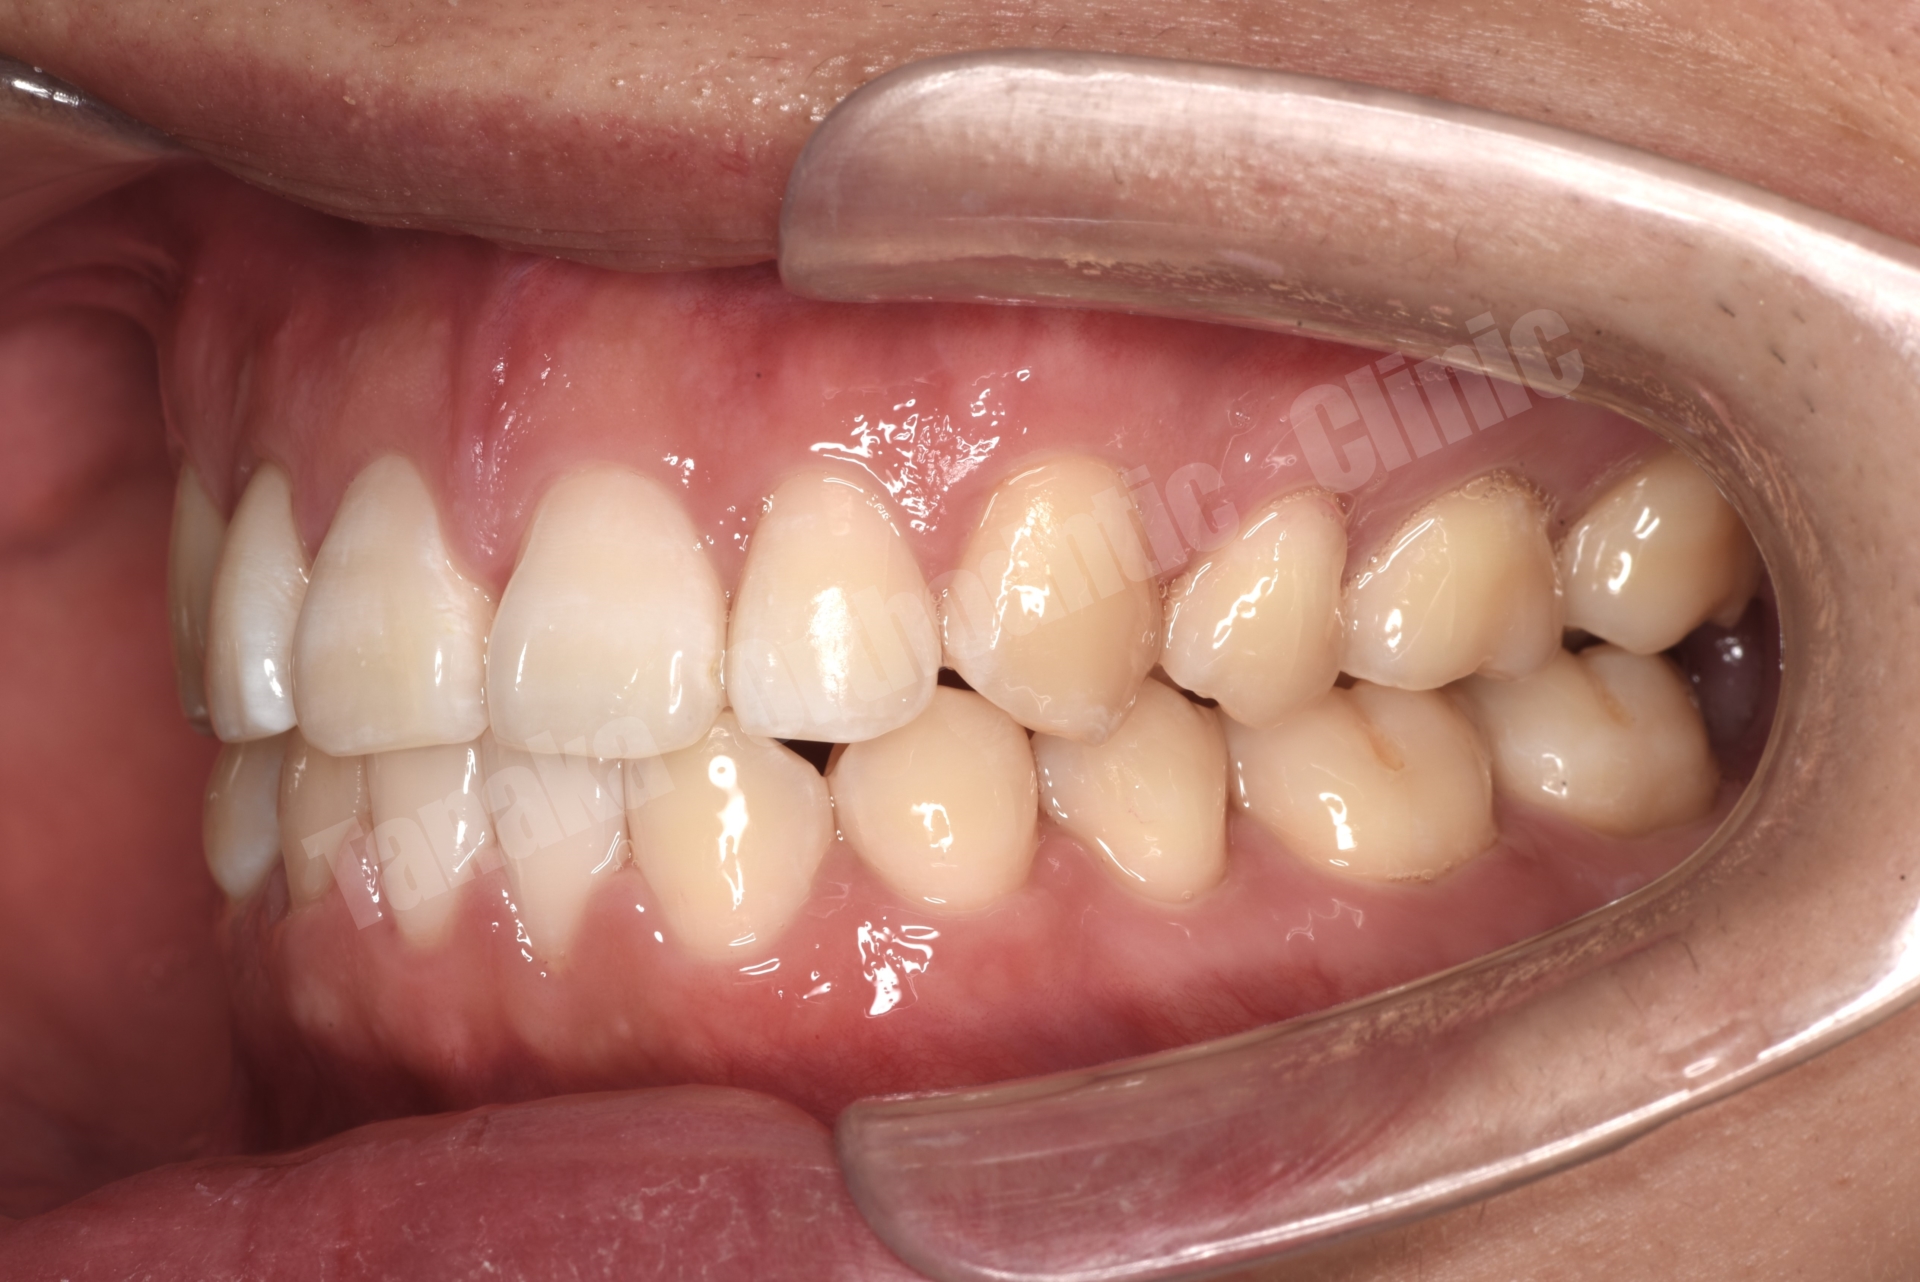

【治療後】

| 診断 | 下顎前歯の先天欠如(2本)によるスペースドアーチ、上顎前歯の唇側傾斜、前歯部水平被蓋が大きい、上顎前歯部叢生、両側AngleⅡ級、上下顎両側8番の埋伏歯、全体的に歯根が短い |

| 抜歯/非抜歯 部位 | 抜歯 上顎両側4番 |

| 治療装置 | マウスピース型矯正装置(インビザライン) 顎間ゴム |